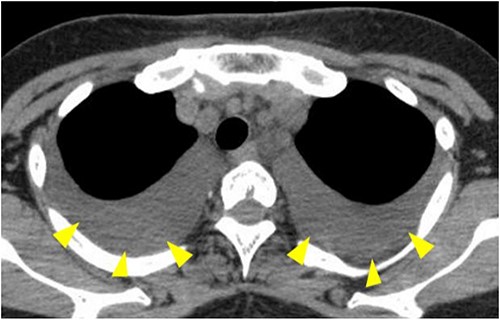

The patient was started on a diet the first day after surgery. On the third day postoperative, she complained of respiratory distress in a supine position, and cough reflex was observed during deep inhalation. Chest X-rays and CT showed pleural effusion in both lower lung fields (Fig. 3), and chylothorax was suspected based on the intraoperative and postoperative clinical findings. Approximately 600 mL of yellowish-white pleural fluid was aspirated during bilateral thoracic puncture. Furthermore, no swelling of the neck was observed, and the contents of the neck drain were serous and had a concentration of 15 mg/dL of triglyceride, which was within the normal range. Therefore, no evidence of chyle leakage was observed in the neck. On the other hand, the triglyceride concentration of the pleural effusion was 705 mg/dL, which was significantly higher than that of the standard value. The patient was diagnosed with bilateral chylothorax without cervical chyle, according to the above results, but pleural effusion subsequently improved and respiratory distress disappeared. A low-fat diet was started on the fourth day after surgery, and all neck drains were removed on the eighth day postoperative. The pleural effusion on the chest radiograph disappeared 16 days after thoracentesis (Fig. 4), and postoperative chemoradiotherapy was performed since extra-nodal spread was observed in the left cervical lymph nodes (level II and III), determined through histopathology.

CT showing pleural effusion in both lower lung fields (arrowheads).